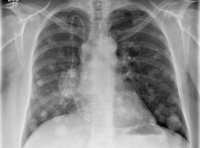

Диагноз выставляется с учетом анамнеза, клинических проявлений, результатов инструментальных и лабораторных исследований. Пациентов с подозрением на метастазы в легких направляют на рентгенографию грудной клетки, позволяющую оценивать состояние легочной ткани, определять тип, характер и количество вторичных новообразований, наличие выпота в плевральной полости. Пациентам также назначают КТ легких - эта современная методика дает возможность выявлять мелкие метастазы диаметром менее 0,5 в том числе расположенные субплеврально.

При необходимости снизить лучевую нагрузку (при метастазах в легких у детей, при многочисленных исследованиях для выявления первичного очага и метастатических поражений других органов, при продолжительном наблюдении) и подозрении на наличие мелких метастазов проводят МРТ легких - эта методика позволяет обнаруживать вторичные очаги диаметром менее 0,3 Метастазы в легкие подтверждают на основании результатов цитологического исследования мокроты и плеврального выпота или гистологического исследования биоптата, полученного в процессе бронхоскопии, чрескожной пункционной биопсии легкого или (реже) открытой биопсии.